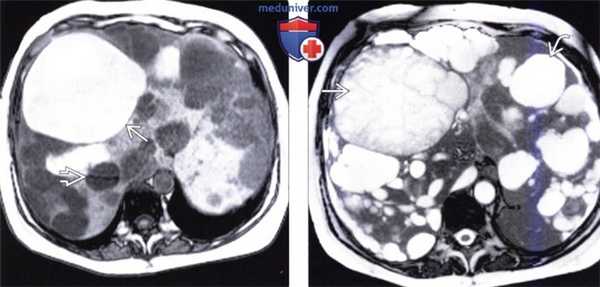

(Слева) На Т1 ВИ GRE opposed-phase МР томограмме определяются множественные кисты печени, обладающие различными сигнальными характеристиками. Некоторые из них гипоинтенсивны, как этого следует ожидать от простых кист с жидкостным содержимым, другие дают промежуточный по интенсивности сигнал. Как минимум в одной из них визуализируется перегородка и неоднородное содержимое, обусловленное «старым» кровоизлиянием.

(Справа) На Т2 ВИ МР томограмме у этого же пациента видна комплексная структура содержимого некоторых кист: неосложненные кисты остаются равномерно гиперинтенсивными, содержимое осложненных кист становится неоднородным.